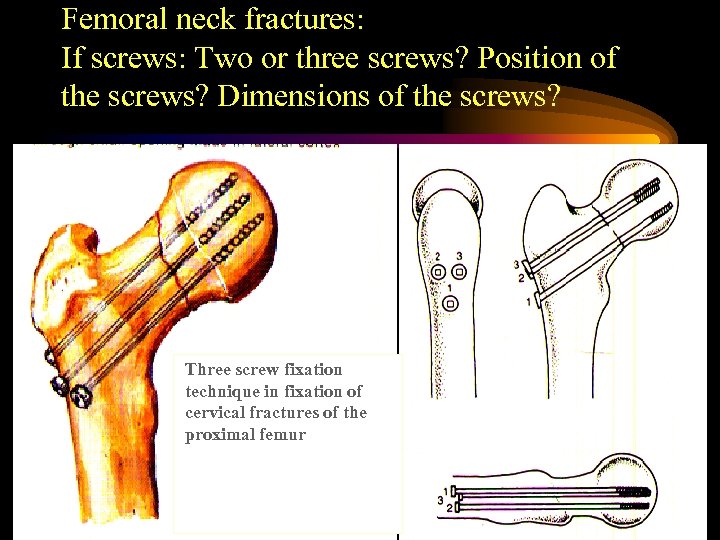

Femoral neck fractures: If screws: Two or three screws? Position of the screws? Dimensions of the screws? Three screw fixation technique in fixation of cervical fractures of the proximal femur

Femoral neck fractures: If screws: Two or three screws? Position of the screws? Dimensions of the screws? Three screw fixation technique in fixation of cervical fractures of the proximal femur